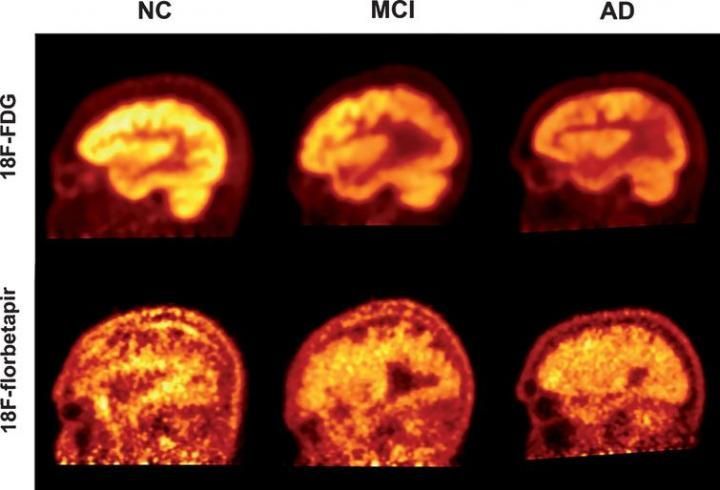

(PHILADELPHIA) — While the presence of beta-amyloid plaques in the brain may be a hallmark of Alzheimer's disease, giving patients an amyloid PET scan is not an effective method for measuring their cognitive function, according to a new study from researchers in the Perelman School of Medicine at the University of Pennsylvania and Thomas Jefferson University. The researchers concluded that fluorodeoxyglucose (FDG) PET, which measures the brain's glucose consumption as a marker of neural activity, is a stronger approach for assessing the progression and severity of Alzheimer's and mild cognitive impairment (MCI) as compared to florbetapir-PET scans, which reveal amyloid protein deposits in the brain. This suggests that FDG-PET is also a better means for determining the effectiveness of Alzheimer's therapies, as well as tracking patients' disease advancement, in both clinical and research settings. Results of this study are detailed in the August issue of the Journal of Alzheimer's Disease.

Two of the most significant biomarkers found in Alzheimer's are decreased glucose uptake and the accumulation of amyloid plaques in the brain. PET scans use different radioactive drugs, called radiotracers, to measure these biomarkers within the brain tissue of patients with cognitive impairment. FDG-PET is one of the most commonly used imaging techniques to diagnose Alzheimer's. However, in recent years, several other radiotracers, such as florbetapir, have been developed to detect the deposition of amyloid plaques.

In this study, the researchers evaluated 63 individuals, including 19 with clinically diagnosed Alzheimer's disease, 23 with MCI, and 21 healthy individuals. The study participants underwent both FDG- and florbetapir-PET imaging. They were then assessed with a Mini Mental Status Examination (MMSE), a widely used diagnostic test for detecting and assessing the severity of cognitive impairment. The researchers used a novel "global quantification approach" to generate data from five different regions of the brain, which were correlated with the results from the MMSE scores.

The study revealed that both FDG- and florbetapir-PET scans are able to effectively discriminate the individuals with dementia from the healthy control group. However, when compared with the MMSE scores, the correlation between low cognitive performance and high levels of amyloid was significantly weaker than the correlation between FDG and low cognitive performance for all groups included in the study. This suggests that FDG-PET is a more sensitive indicator of cognitive decline.